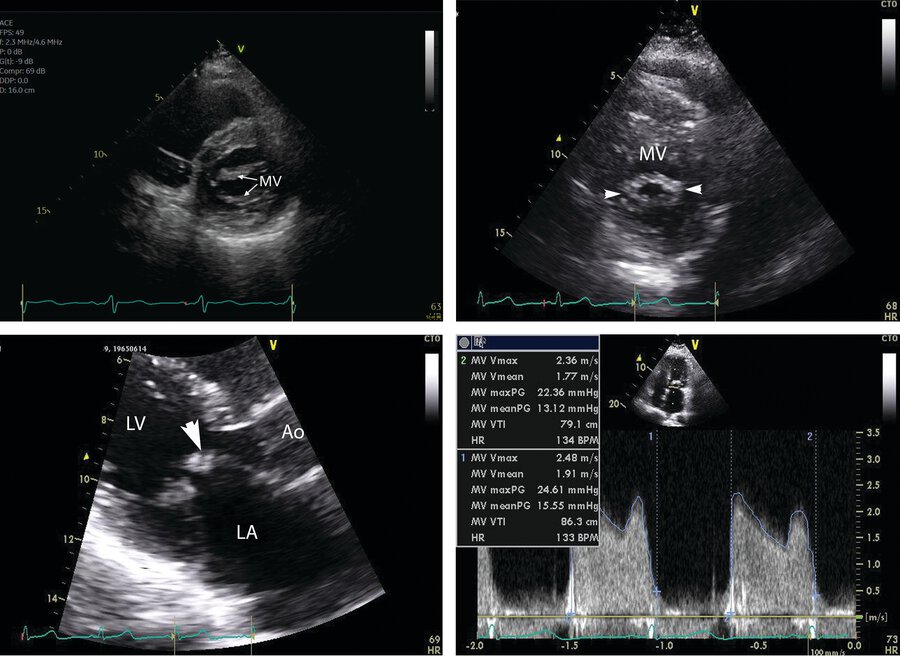

What is the hallmark finding of Rheumatic MS?

In the bottom left panel, diastolic doming (arrowhead) is present with a “hockey stick” deformity from mitral stenosis.